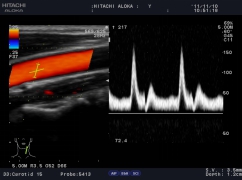

精確血流成像

智能識別血流運動和組織運動,使血流更充盈,組織邊界更清晰。

實時三同步

B型、彩色和頻譜多普勒三種模式同時實時顯示,獲得更精確地采樣定

位,更直觀進行對比分析。